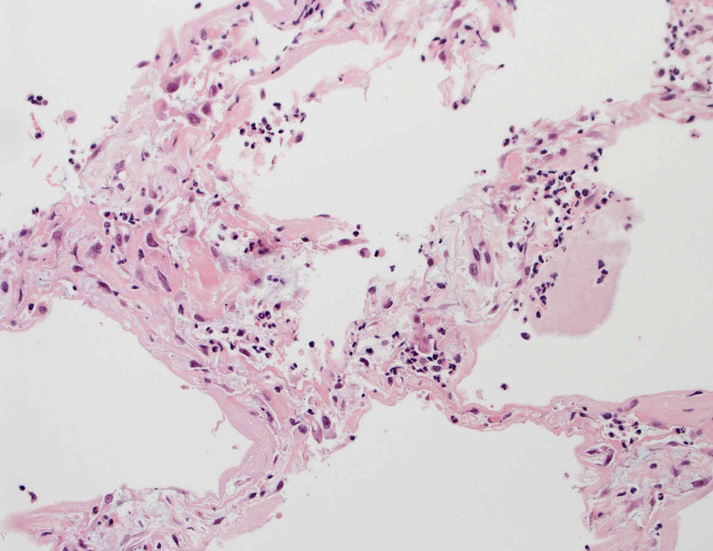

肺の病理所見

lung01.jpg

lung02.jpg

lung03.jpg

lung04.jpg

Fig.01Fig.02Fig.03Fig.04